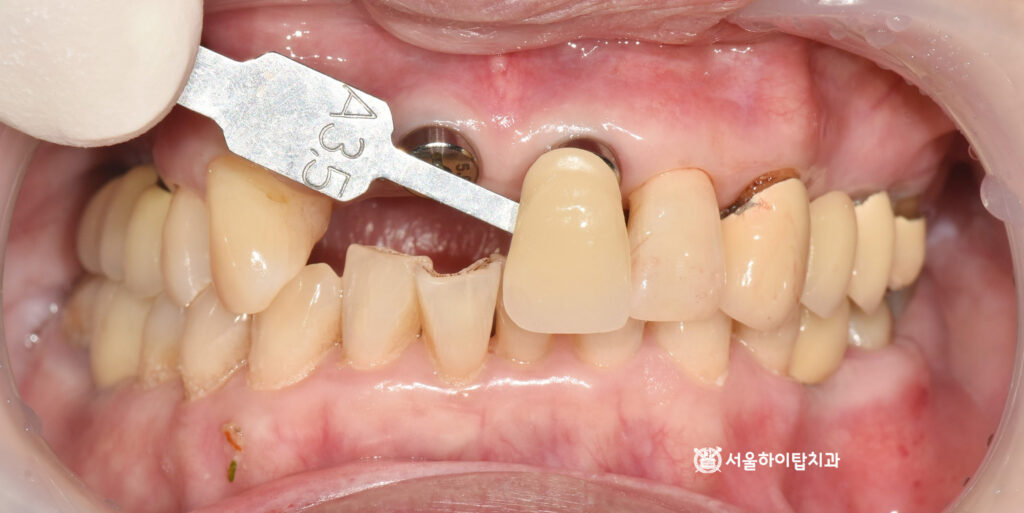

1. 초진

만수동 치과 에서 표시한 부분을 보면,

부러진 자연치와 일부 정출된

모습을 확인할 수 있습니다.

이러한 문제가 동시에 나타난 이유는,

충치로 인한 치질 약화와 골 소실이

함께 진행되었기 때문입니다.

충치로 인해 부러지면

남아 있는 치질의 강도가 떨어지고,

치조골이 흡수되면서 치아를 지탱하는

기초 구조도 약해집니다.

결국 이러한 변화가 겹치면

점차 정출되거나 사이가 벌어지는

현상이 나타나게 됩니다.

즉, 자연치 자체의 훼손과

주변 지지조직의 약화가

복합적으로 작용한 결과입니다.

이에 따라 구강 내 사진을 보면

충치로 인해 부러진 파절면이

뚜렷하게 관찰됩니다.

또한 뼈의 흡수로 인해

정출되고 앞니 사이가 벌어진